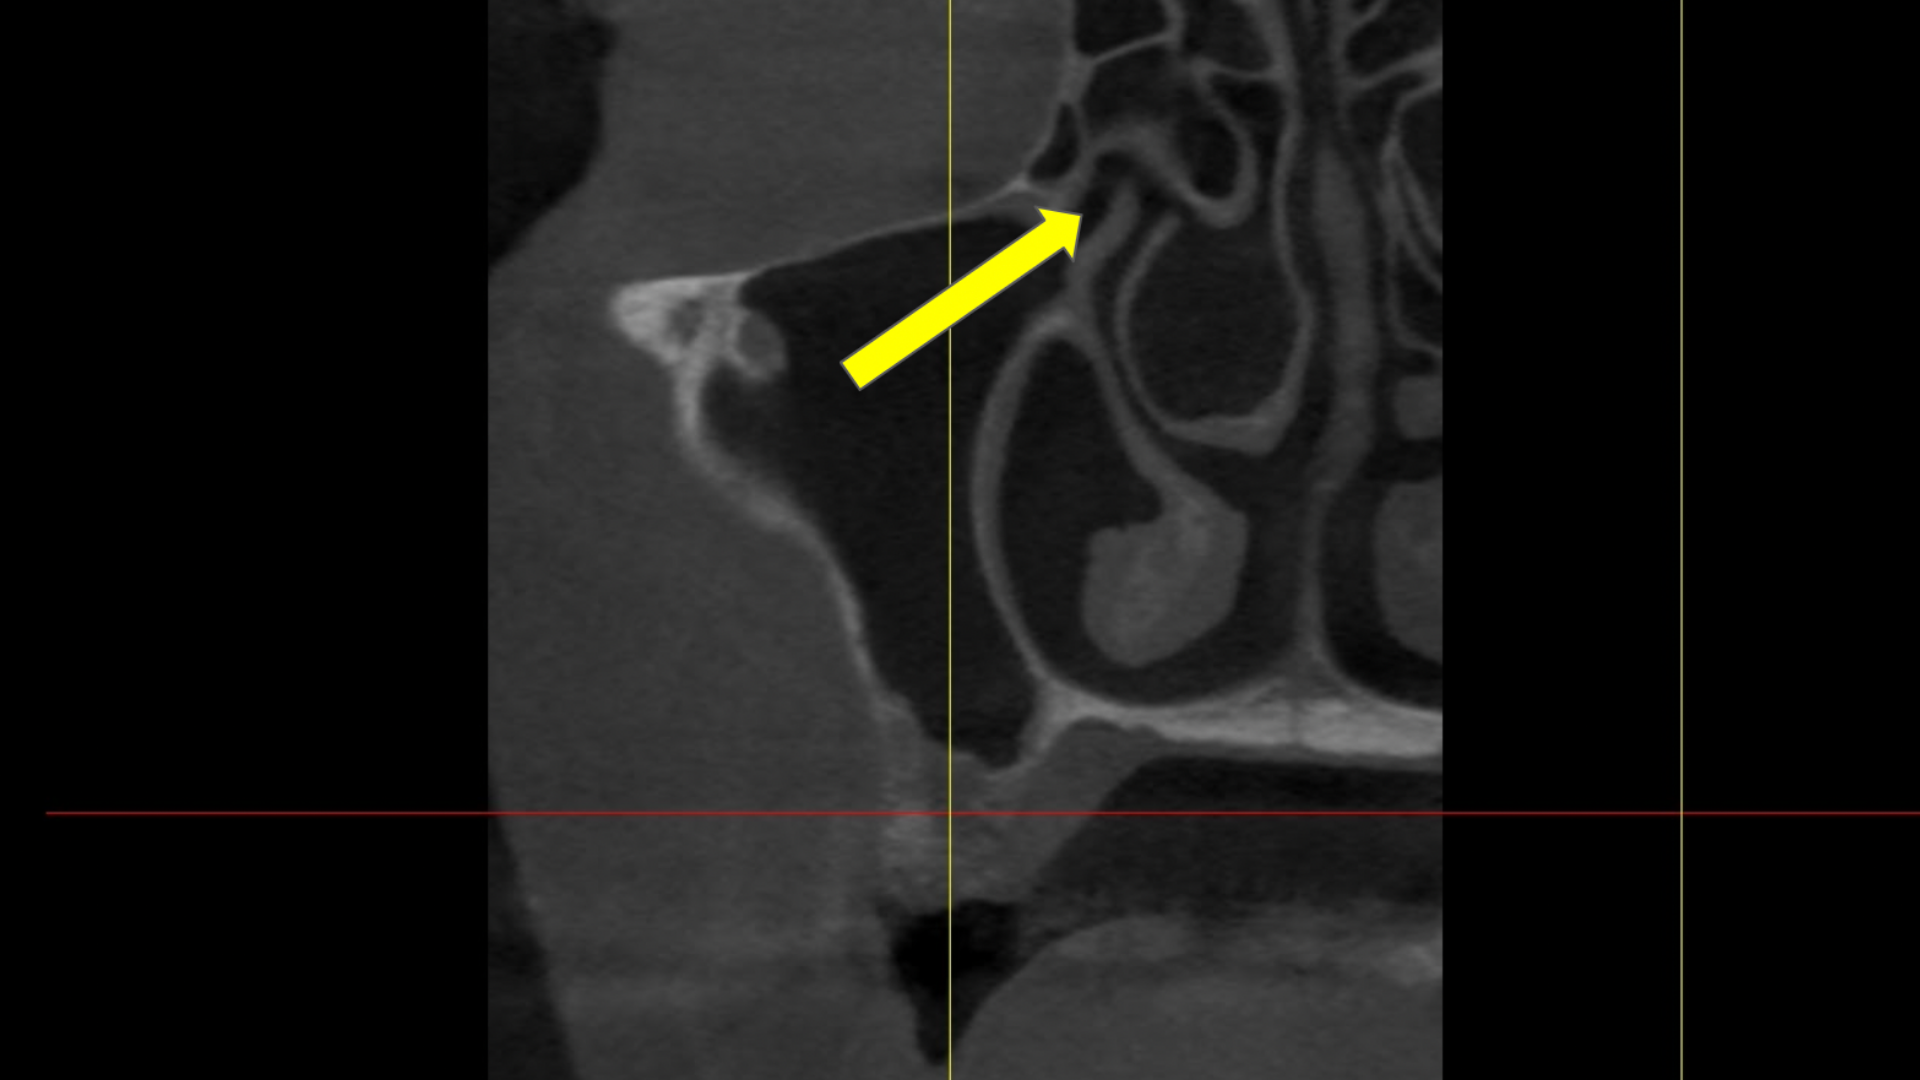

- How to diagnose the exact sinus lift method for each implant patient

- When a crestal sinus lift is indicated

- When a lateral window sinus lift is indicated

- Gain clarity on sinus anatomy and what to look for when considering sinus lifts